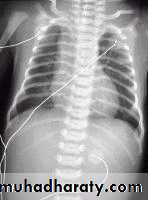

This is a radiograph of a 1-day-old infant with a moderate-sized

congenital diaphragmatic hernia. Note the air- and fluid-filled bowel loopsin the left chest, the moderate shift of the mediastinum into the right chest,